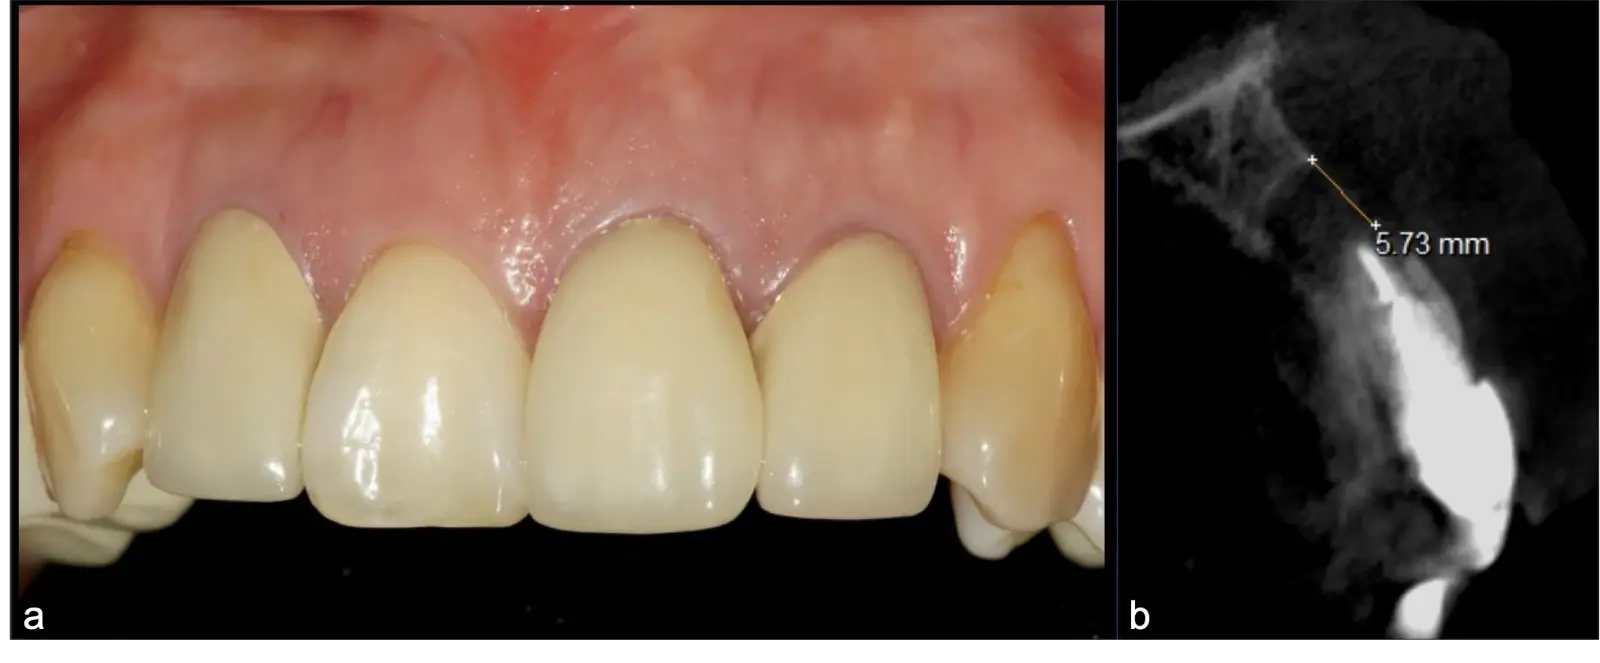

La microcirugía endodóntica apical busca conservar la mayor cantidad de longitud de raíz y de hueso circundante sano para no afectar la estabilidad de la pieza.11 Por ello, es ideal el uso de microscopios, elementos de magnificación, instrumental específico (insertos de ultrasonido endodónticos) y materiales de sellado eficientes para el tratamiento retrogrado. Su éxito es alto y evidencia una cicatrización ósea completa en el 74% de los casos al año de tratamiento.12 Cabe destacar que este logro está asociado también, a predictores propios de cada paciente, como la edad, tipo de pieza, profundidad de sondaje y extensión de la lesión.1 El uso complementario de la tomografía computarizada es resaltante como el instrumento imagenológico de elección para la etapa de planificación microquirúrgica,13 ya sea para una ejecución a mano alzada o con guías prefabricadas.14,15

El procedimiento se inicia colocando anestesia y elevando un colgajo mucoperióstico a espesor completo3 (incisión semilunar o intrasurcular con/sin protección papilar) y exponiendo la zona. En seguida se realiza la enucleación de la lesión, eliminando16 o creando una ventana17 en la lámina cortical que contiene el área del ápice; este retiro óseo se realiza con los insertos de forma aplanada dentada o inserto con cobertura diamantada plano o redondo, recordando ser lo más conservador posible (Figura 5).